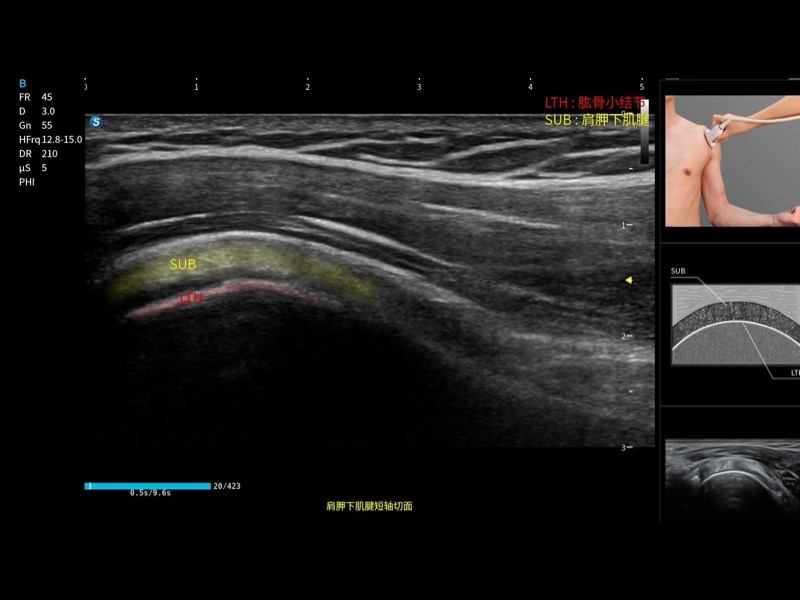

指导操作者进行标准切面的正确扫查,涵盖丰富应用场景,为新晋医生提供实用的参考指导。

将测量、体标和注释等关键内容整合到一个页面中。精简界面,诊断更有针对性。

可助力简化工作流程,同时提升操作标准化程度,并减少按键次数,缩短检查时间。